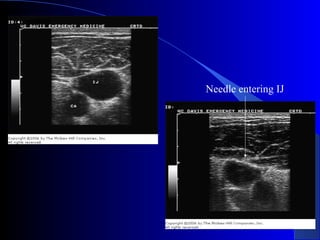

Ultrasound-Guided CentralUltrasound-Guided Central

Venous AccessVenous Access

 Becoming standard of care

 Vein is compressible

 Vein is not always larger

 Vein is accessed under direct

visualization

 Helpful in patients with

difficult anatomy

Needle entering IJ

Ultrasound-Guided CentralUltrasound-Guided Central VenousAccessVenous Access  Becoming standard of care  Vein is compressible  Vein is not always larger  Vein is accessed under direct visualization  Helpful in patients with difficult anatomy